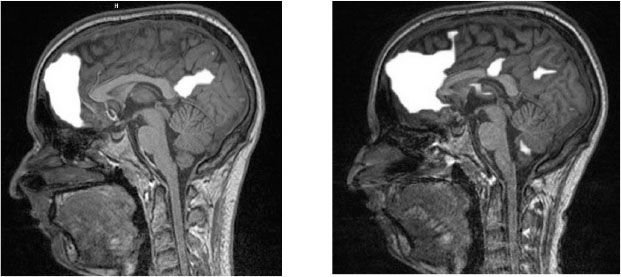

Мозговая активность Кейси до начала лечения (слева) и после его окончания (справа)

Снимки мозга Кейси поражали воображение. Они демонстрировали явные изменения в медиальной префронтальное коре (cortex praefrontalis), прилежащем ядре (nucleus accumbens) и передней островковой доле (anterior insula). У этих участков мозга две общие черты: все они звучат на латыни как заклинания из Гарри Поттера[18], и все они участвуют в обработке болевых ощущений[19].